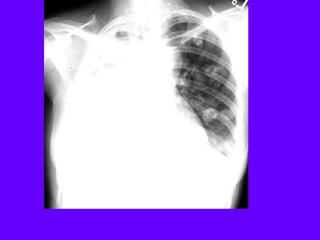

Lung Cancer / Squamous Cell

Mass density

Anterior segment of LUL

Thick wall cavitation

SquamousCell Carcinoma

Thick wall

Fluid level

Full hilum